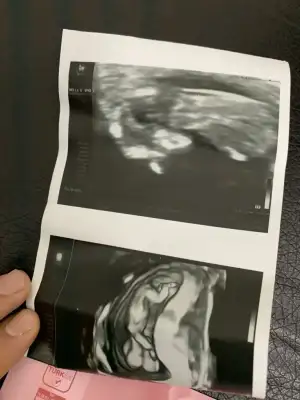

Bu da arkadaşımın bebişinin 12. haftasından görüntüsü. Yine tahmin rica edeceğiz sizden. Sevgiler

Eklentiler

• M 12 hafta.webp

M 12 hafta.webp

10,9 KB · Görüntüleme: 54